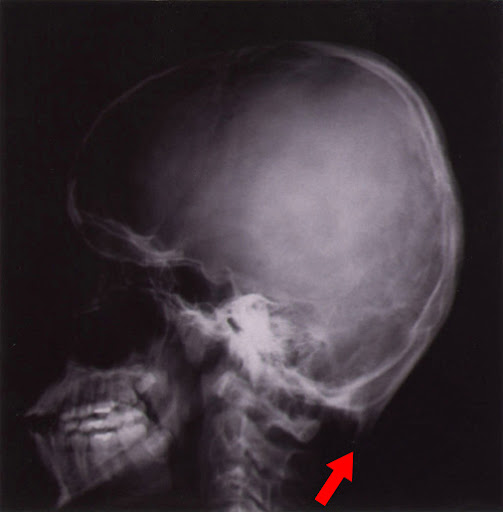

頭のレントゲンで後頭部の下の方に、小さな角のような骨が認められます。

「後頭骨」を「オキシピタル」「角」が「ホーン」と言う意味です。